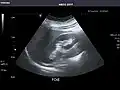

Liver

Ultrasonography of the liver with some standard measurements[6]

In patients with deranged liver function tests, ultrasound may show increased liver size (hepatomegaly), increased reflectiveness (which might, for example, indicate cholestasis), gallbladder or bile duct diseases, or a tumor in the liver.

Ultrasonography of liver tumors involves two stages: detection and characterization. Tumor detection is based on the performance of the method and should include morphometric information (three axes dimensions, volume) and topographic information (number, location specifying liver segment and lobe/lobes). The specification of these data is important for staging liver tumors and prognosis. Tumor characterization is a complex process based on a sum of criteria leading towards tumor nature definition. Often, other diagnostic procedures, especially interventional ones, are no longer necessary. Tumor characterization using the ultrasound method will be based on the following elements: consistency (solid, liquid, mixed), echogenicity, structure appearance (homogeneous or heterogeneous), delineation from adjacent liver parenchyma (capsular, imprecise), elasticity, posterior acoustic enhancement effect, the relation with neighboring organs or structures (displacement, invasion), vasculature (presence and characteristics on Doppler ultrasonography and contrast-enhanced ultrasound (CEUS).